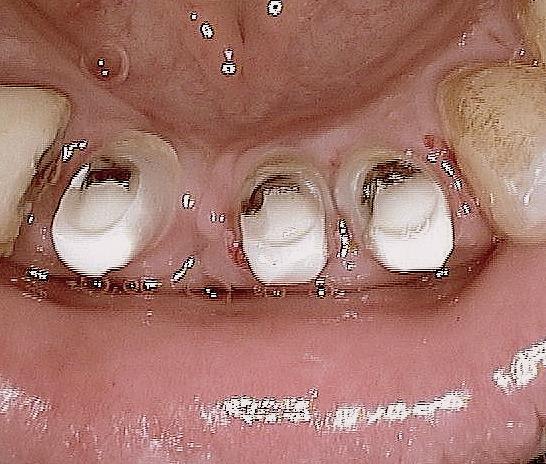

> feriez-vous le même traitement a un patient de 30 ans???

> problèmes de distance inter-implants

Pour un patient de 30 ans, pourquoi pas.Mais on peut implanter seulement 6 à 8 pour une prothèse fixée.Et 4 implants pour une prothèse amovible dans la mandibula.

Pour la distance inter-implants c est une bonne remarque, le distance réglementaire est de 2/3mm en méthode conventionelle , ici c´est une variante du flapless en forant de manière à condenser l´os via un foret à 3 faces. En préservant le périoste on a remarqué que cette distance réglementaire pouvait être plus petite. C est une observation , qui marche (en flaples) dans ma pratique et dans celles de mes confrères Allemands, à ma connaissance pas enormément documenté . Ceci dit il y a un livre en francais qui en parle "implantologie flapless" de Byung Ho Choi et wilfried Engelke (Pr de Göttingen).

Sur le cas posté au début la dernière radio est après deux ans post OP. Ci dessous un autre exemple.

Les 12 premières photos sont un même cas avec implantation immédiate.

Le deuxième cas c est les photos 13 14 15 , (la photo 14 et 15 est après 5 ans)

Le dernier cas (3 dernieres photos), a été realisé il y a 5 ans il n y a pas de problème, je ne trouve pas les radios malheureusement je vais chercher encore un peu dans la journée.

Sur la photo 14 (implants mandibulaires)

Quelle est la longueur des implants ?

J'aime bien ce cas, sauf peut-être pour une certaine proximité des implants, car même si l'os peux être ok, pas facile pour la prothèse et son entretient.